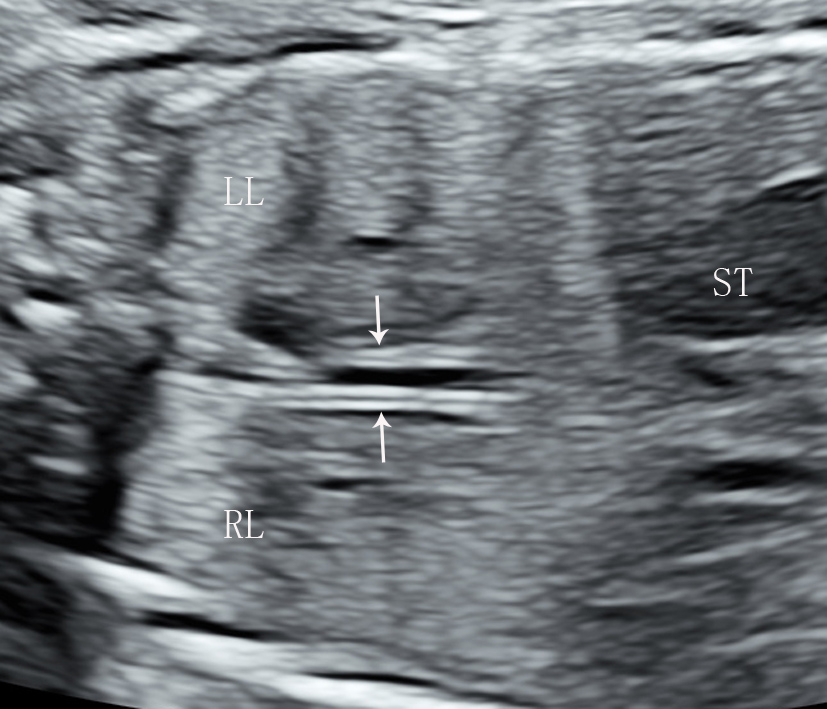

Fig. 2.Longitudinal section of a fluid-filled fetal esophagus,

appearing as a tram-track sign. Longitudinal section of

fetal esophagus imaging in a fetus in the LSA position at 22

Two patterns of longitudinal esophageal sections in fetuses were observed when

collapsed on ultrasound: a tubular structure composed of three hyperechoic layers

(40.4%, 88/218) and a tube composed of multilayered hyperechoic structure

(59.6%, 130/218; Fig. 1). Swallowing actions were observed

in 28 cases (12.8%, 28/218; Fig. 2). The fetal esophagus was fluid-filled and

exhibited an appearance similar to a tram-track sign. The

mean esophageal length on longitudinal section was 25.4